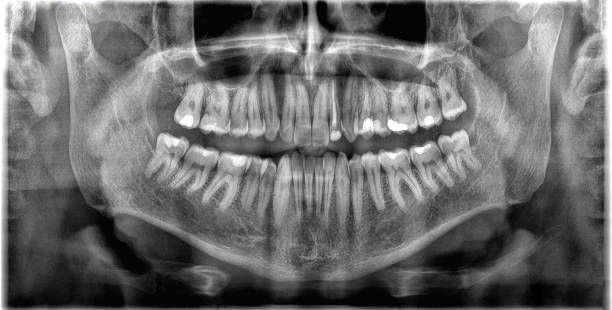

ORTHOPANTOMAGRAPH

Now that's a mouthfull ! Luckily, most dentists will refer to it as a OPG for short.

This type of radiographic image will often be taken if you are a new patient to the Practice [for screening purposes], or if your wisdom teeth might require removing. It is a good way to view both upper and lower jaws, sinuses and TMJ joints [your jaw joints] all at once.